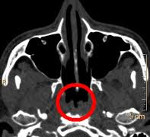

• Лучевые методы диагностики. Результаты КТ и МРТ носоглотки отображают наличие круглого полостного образования размером от 0,5 до 4,5 см с четкими контурами и гладкой внутренней поверхностью, расположенного по срединной линии глотки. У некоторых больных эта структура может иметь дренирующее отверстие.